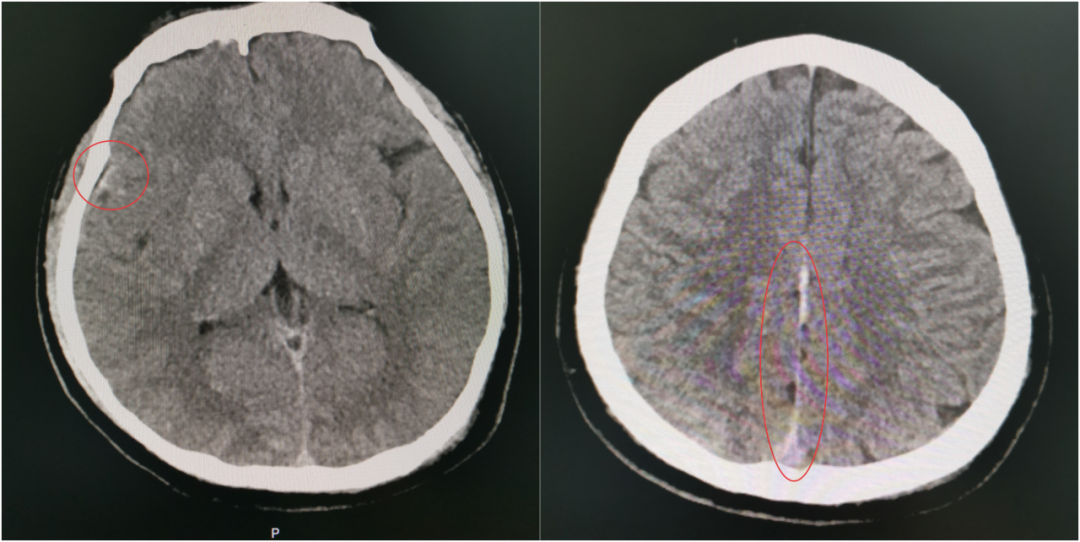

当第二次 CT 提示出现硬膜外血肿、蛛网膜下腔出血范围进一步扩大时,虽然符合预判,但每个人都清楚:出血量和点位的不可控,血肿扩大可能压迫脑组织,任何微小变化都可能改写结局,之前的一系列努力可能功亏一篑。

伤情再次变化,出血范围扩大